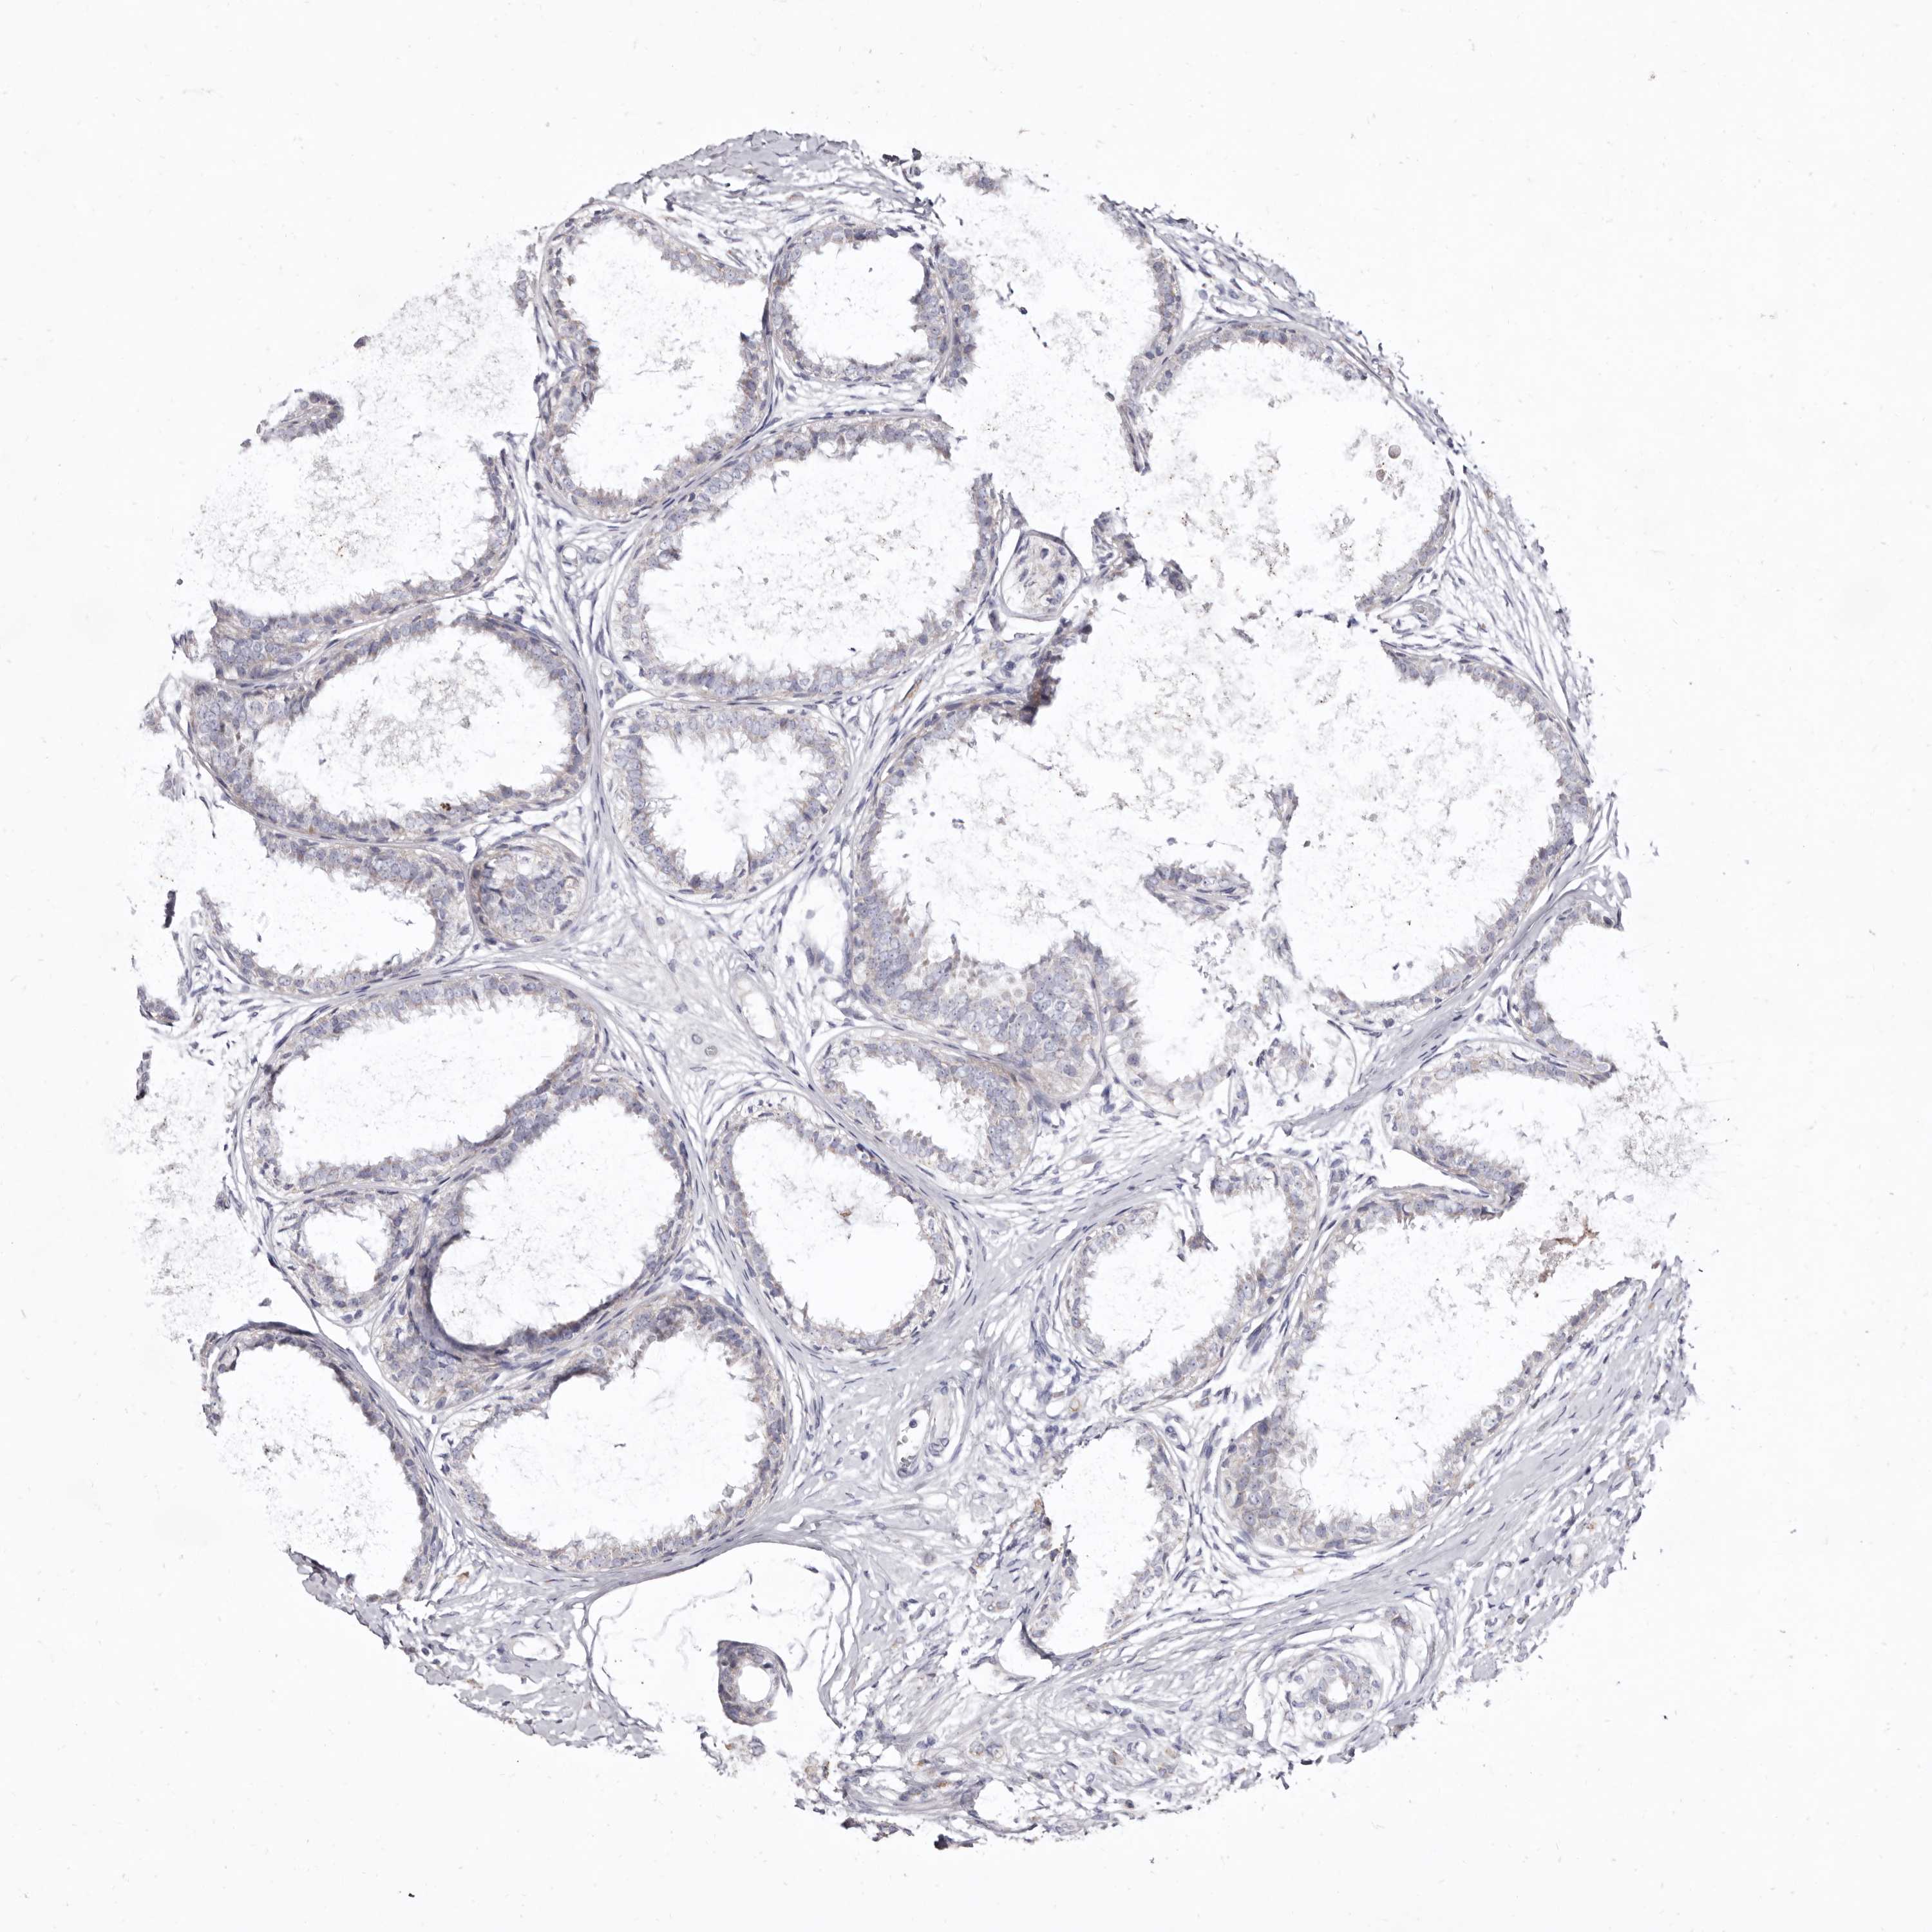

CANCER BREAST CANCER Show tissue menu

BRCA TCGA BRCA VALIDATION PROTEIN EXPRESSION